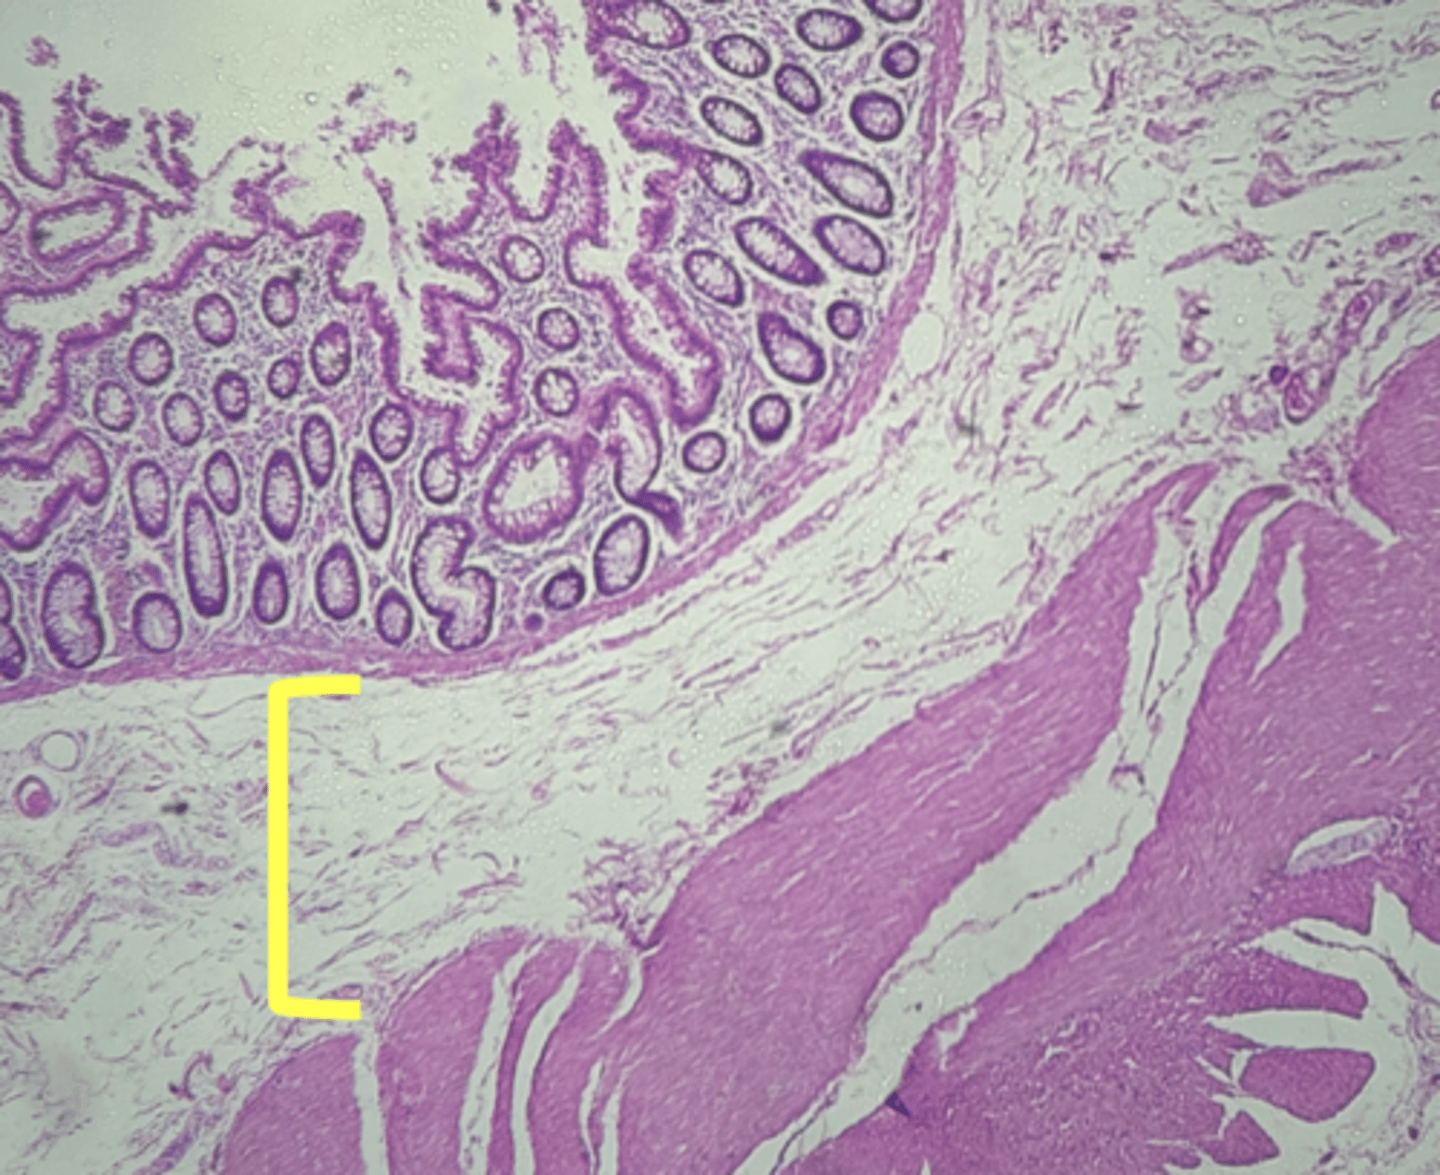

A- Esophagus

B- Stomach

Name the Tissue A & B

Esophagus

name the tissue

stomach